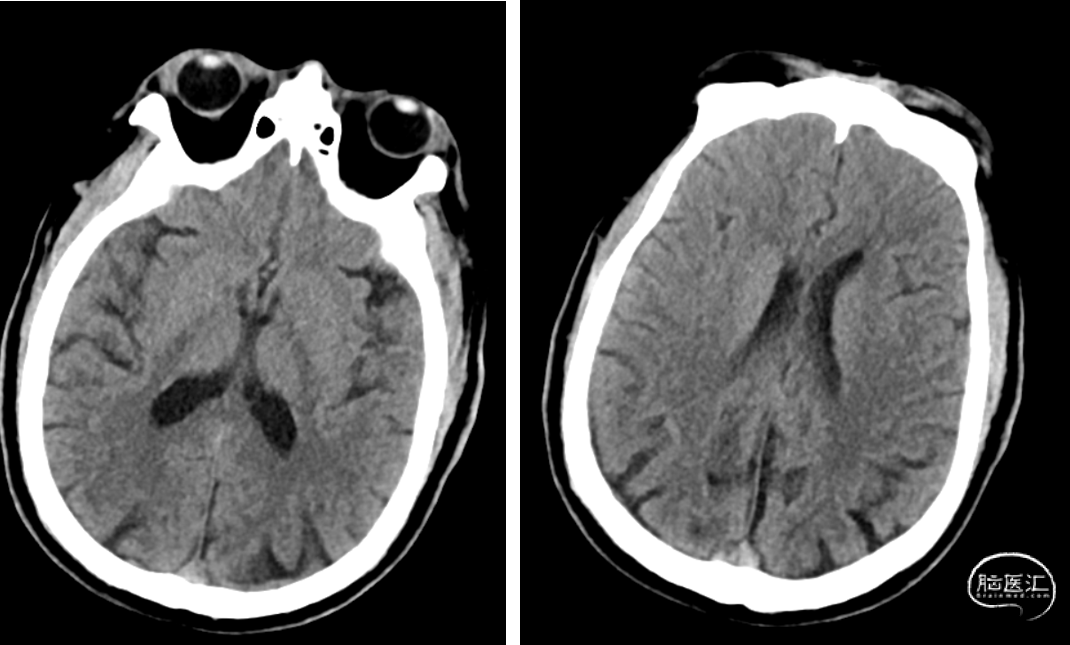

MRA:右侧颈内动脉未见显示。血管壁平扫及增强扫描成像示管壁不规则增厚并呈较明显强化,边缘不规则增厚,内缘欠光滑,中央部分未见强化

T2灌注增强扫描示:右侧额颞顶叶局部灌注异常,MTT、TTP延长,CBF、CBV示右侧颞叶局部区域稍减低。余脑实质未见异常灌注征象。

术后CT